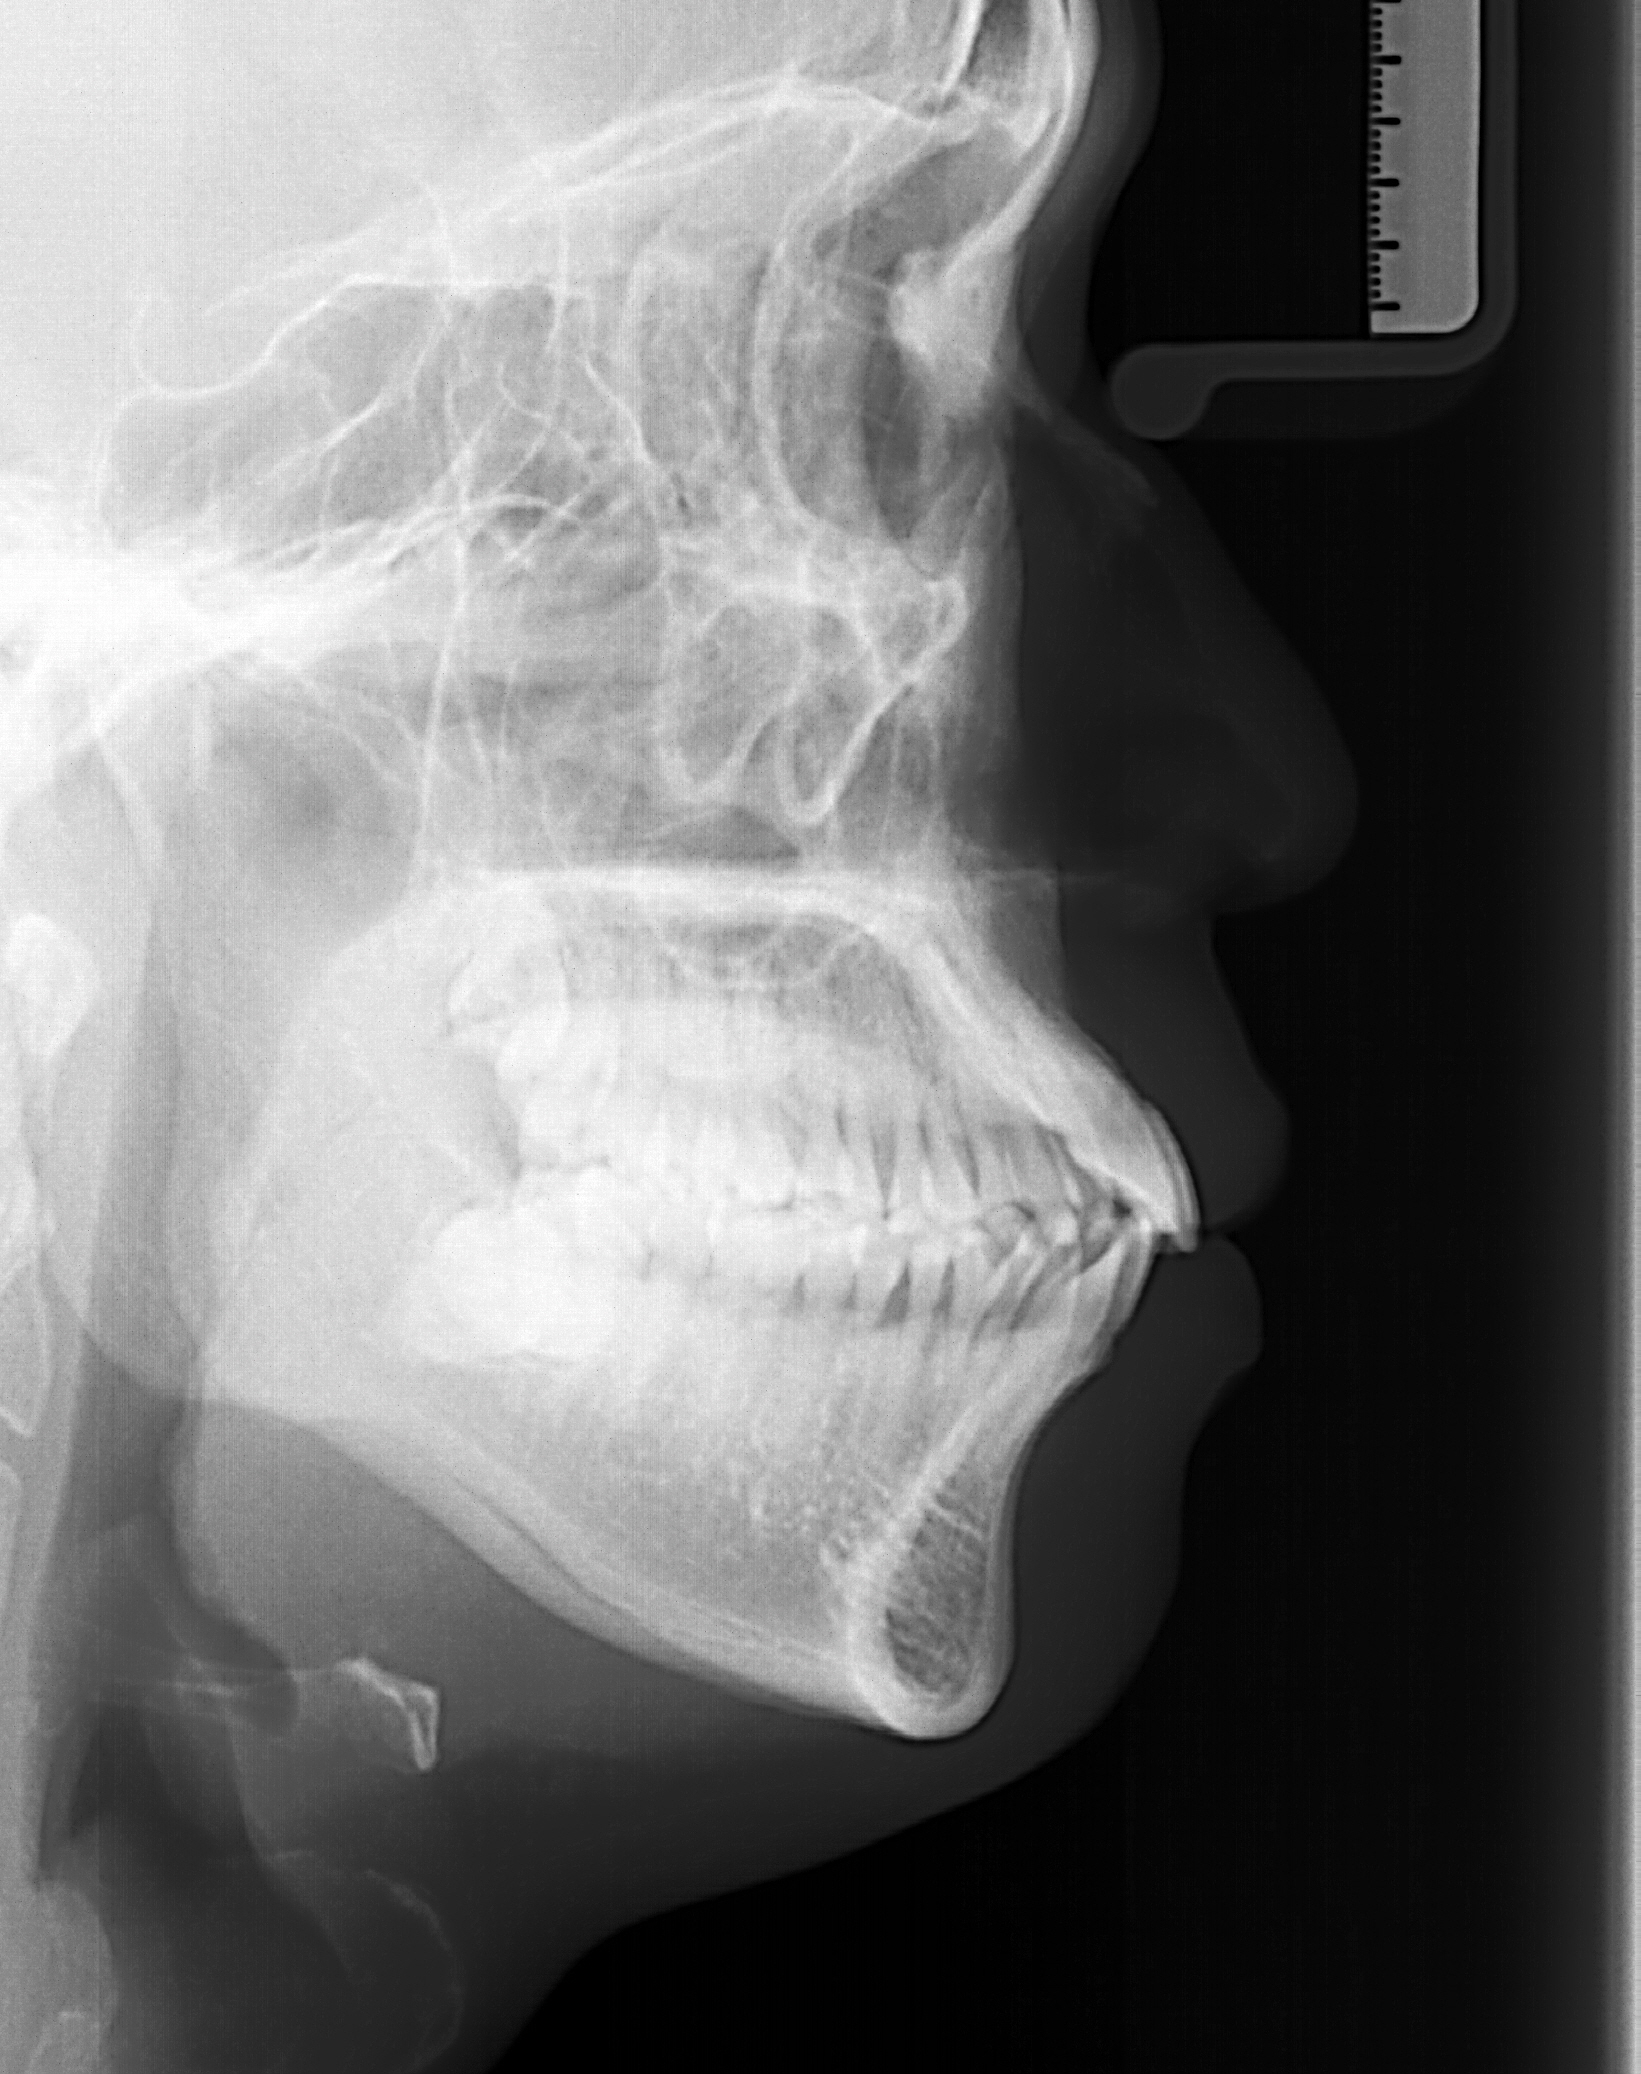

돌출입교정 잇몸돌출인지 치아돌출인지 봐 주세요. 교정 하고파 13년 전 교정할려고 생각 중인데 잇몸돌출인 경우 일반적인 교정으로는 효과가 별로 없다는 얘길 듣고 고민 끝에 사진을 올립니다. 저 같은 경우 잇몸돌출인지 치아돌출인지 궁금합니다. 첨부파일: 2 세팔로1.jpg (1.19MB) 다운로드: 32 사진.jpg (469.9KB) 다운로드: 53 추천 0 비추천 1 교정 하고파